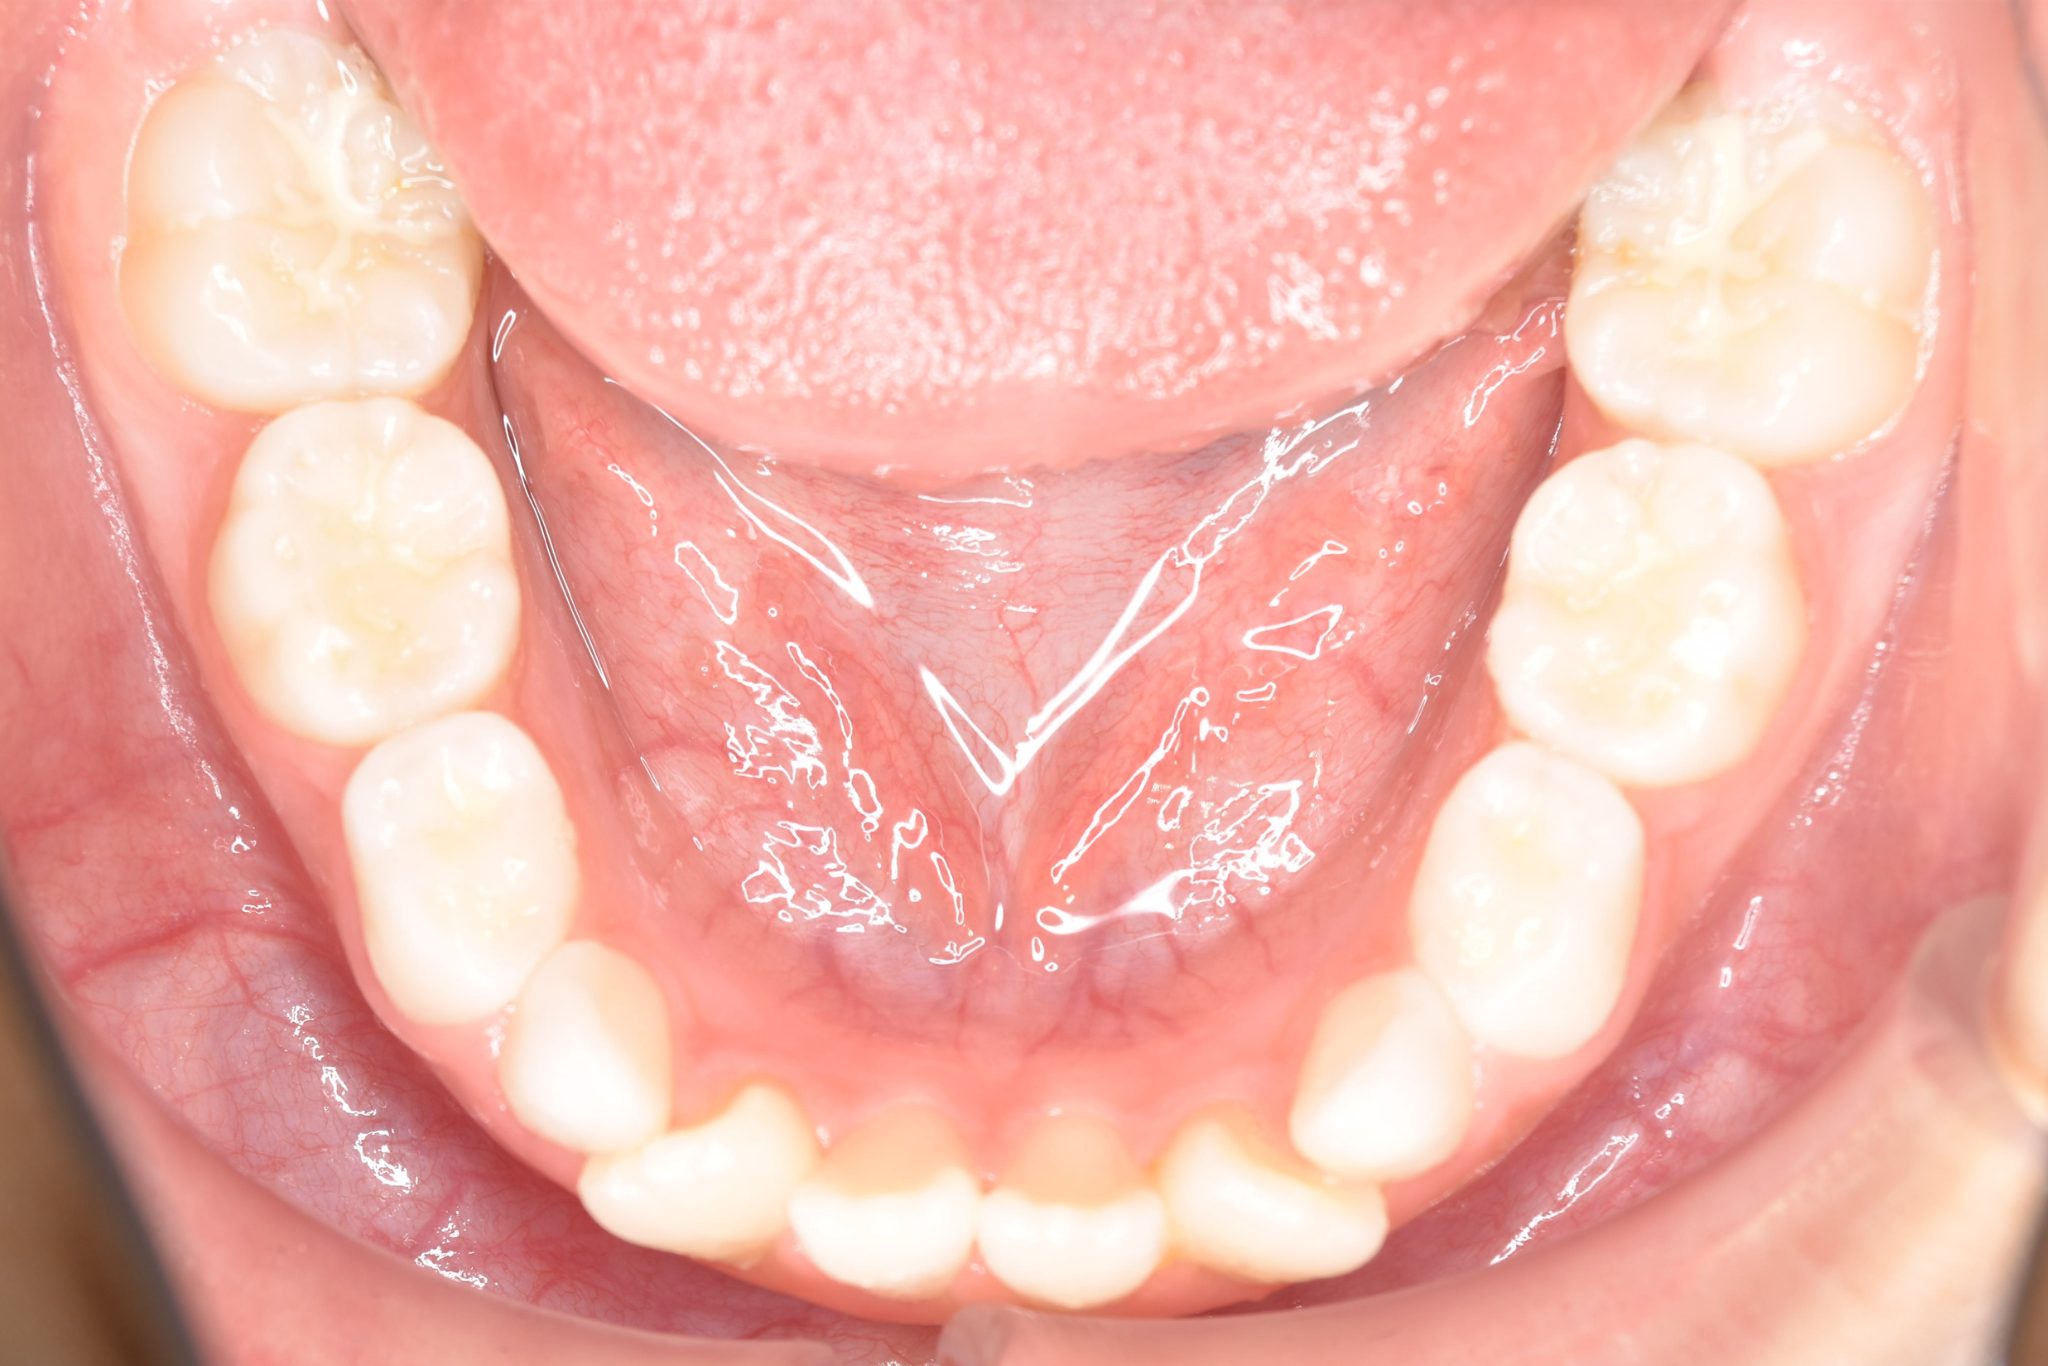

子どもの矯正治療|症例_68 Case

主訴 受け口

施術内容 上顎急速拡大装置と下顎リンガルアーチを用いて上下顎骨を拡大した。

上顎前方牽引装置を用いて上顎骨を前方に成長促進させた。

その後マウスピース型矯正装置で歯牙を配列し良好な咬合を獲得した。

治癒期間 2年9ヶ月間